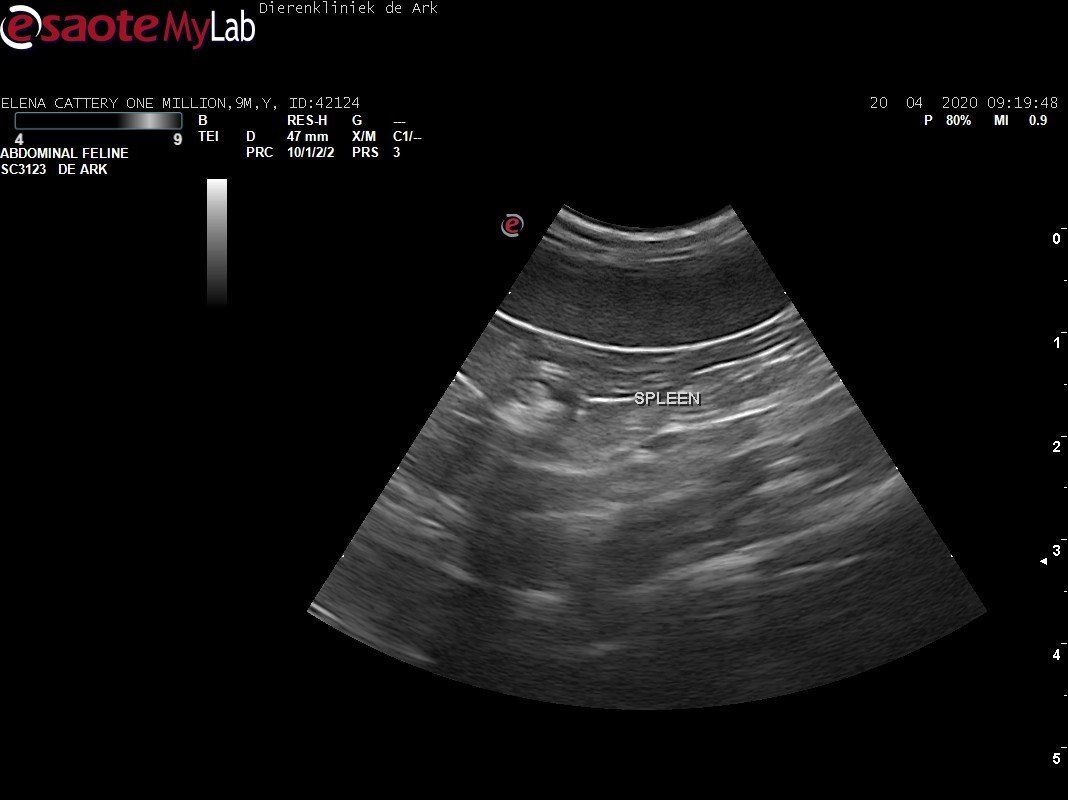

3,200 kg , echo en nieuw bloedonderzoek gedaan wat perfect ging door middel van gapabetine

Voor de garanties en om recht te hebben op medicatie bij herval eist Mutian diverse onderzoeken en controle momenten. Dit zijn bloedonderzoeken maar ook zoals hieronder te zien is echo's. Elana is volledig gecontroleerd op afwijkingen, gelukkig waren de echo's goed.

Ook de bloeduitslagen waren in orde, we kregen groen licht om te stoppen met behandelen en de wachtperiode in te gaan.